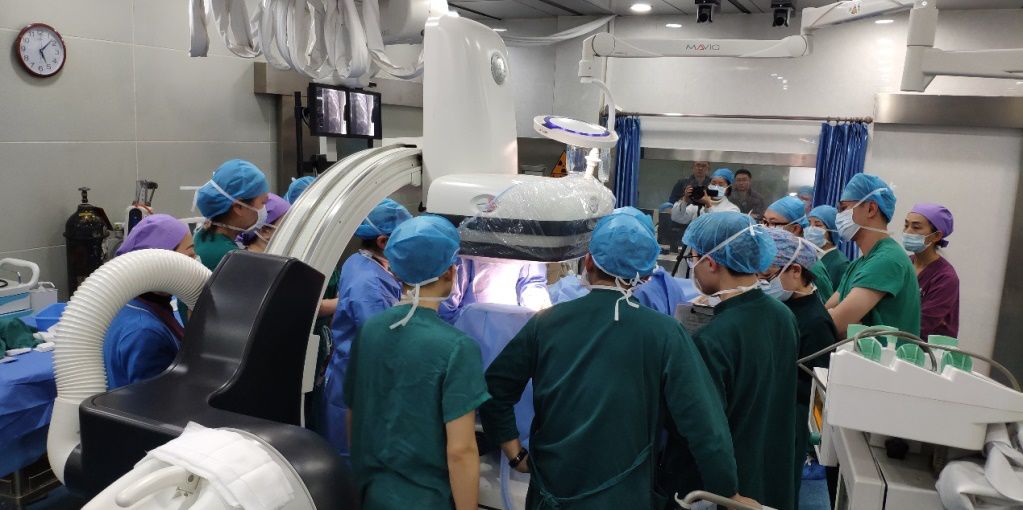

2019年3月14日,在陆军军医大学附属新桥医院心内科黄岚教授,宋耀明教授带领下,本院心内科王江教授起搏团队成功植入重庆市首例全皮下植入式心律转复除颤器(S-ICD)。

手术过程

手术在全身麻醉下进行,于左侧第4肋间沿腋中线走形切开皮肤10厘米,逐层分离皮下组织至筋膜层,作囊袋确保足够深度来容纳装置。于剑突下切开皮肤2厘米,逐层分离皮下组织至筋膜层,通过隧道穿引针连接囊袋,再沿胸骨向上约15厘米处切开皮肤1厘米,逐层分离皮下组织至筋膜层,通过隧道穿引针连接剑突下切口,使用隧道穿引针将45厘米长的3401除颤电极从囊袋经隧道送至剑突下切口,固定电极中段,再使用隧道穿引针将电极经隧道送至胸骨上方切口,固定头端。连接脉冲发生器A209,置入囊袋内,以庆大霉素盐水冲洗各术区及囊袋,逐层缝合皮下组织及皮肤,术区纱布覆盖,包扎,弹力绷带加压包扎止血。

术后行诱颤测试,S-ICD正确识别室颤后成功除颤转复为窦律,除颤能量65焦耳,手术圆满成功。术后患者恢复良好。